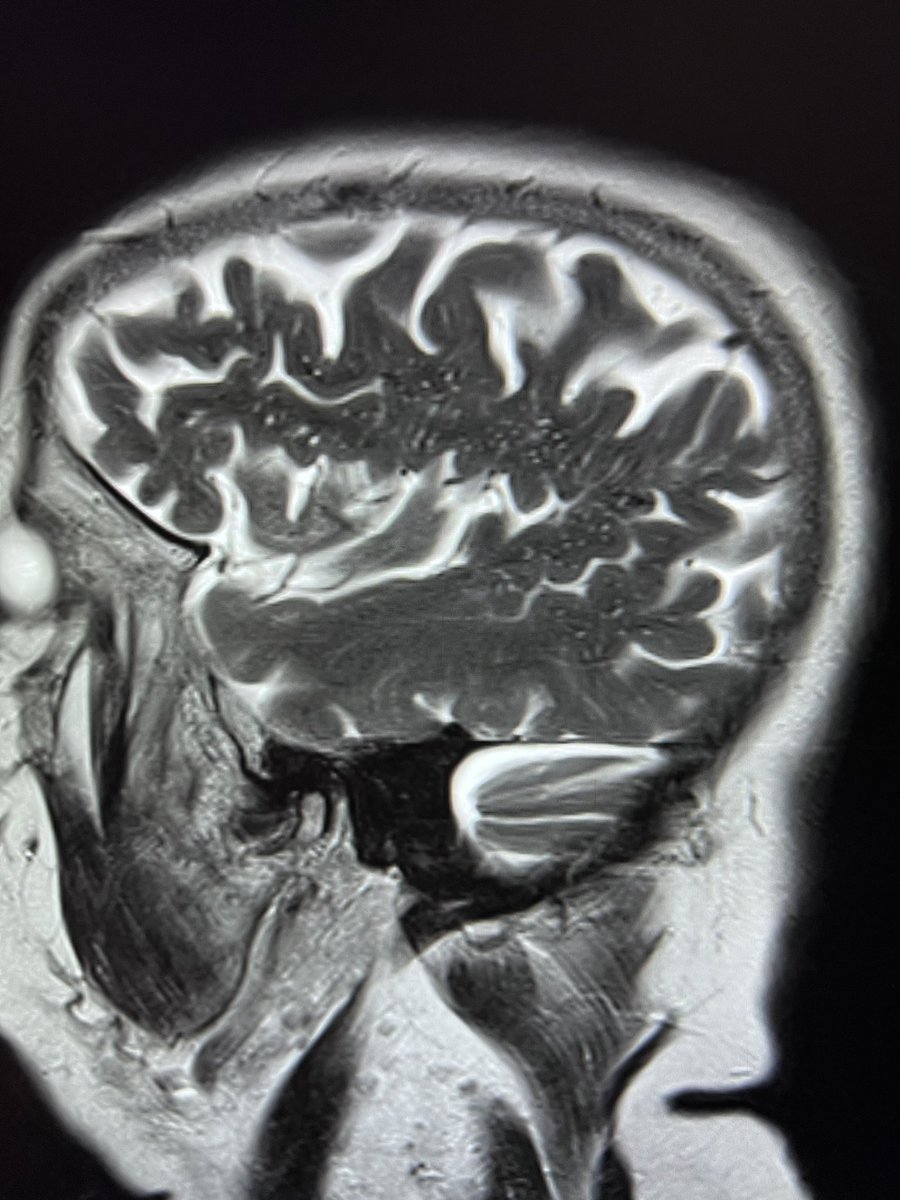

🤿🧠MRI features of Inflammatory Cerebral Amyloid Angiopathy (version 1.0) 🔑 👇🏿 #neurotwitter #NeuroTwitter #NeuroRad #MedTwitter #MedStudentTwitter #MedEd #EndNeurophobia #Neurology #Neurosurgery #RadEd #stroke Gregoire Boulouis World Stroke Academy

🤿🧠MRI features of Inflammatory Cerebral Amyloid Angiopathy

(version 1.0)

🔑 👇🏿

#neurotwitter #NeuroTwitter #NeuroRad #MedTwitter #MedStudentTwitter #MedEd #EndNeurophobia  #Neurology #Neurosurgery #RadEd #stroke <a href="/gboulouis/">Gregoire Boulouis</a> <a href="/WorldStrokeEd/">World Stroke Academy</a>